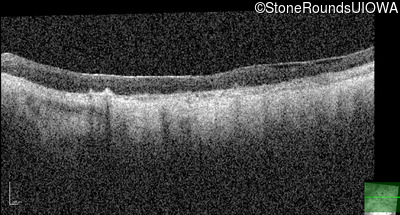

Optical Coherence Tomography - Right - Light Perception

Exemplar / OCT Stack

Optical Coherence Tomography - Left - Light Perception